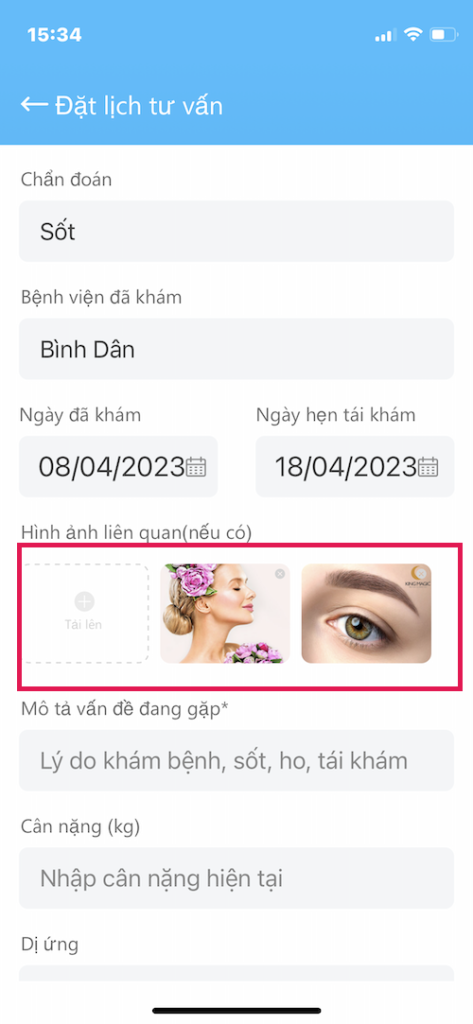

KHAI BÁO THÔNG TIN (tiếp theo)

Toa thuốc, giấy xuất viện là thông tin quan

- Nếu bạn chọn tái khám, sẽ có phần chẩn đoán lần trước là gì?

- Các hình ảnh tải lên có thể cung cấp thông tin quan trọng cho Bác sĩ

- Từ đó biết rõ tình hình của Bạn trước khi bắt đầu cuộc khám

- Sẽ cho kết quả khám tốt nhất, chính xác nhất